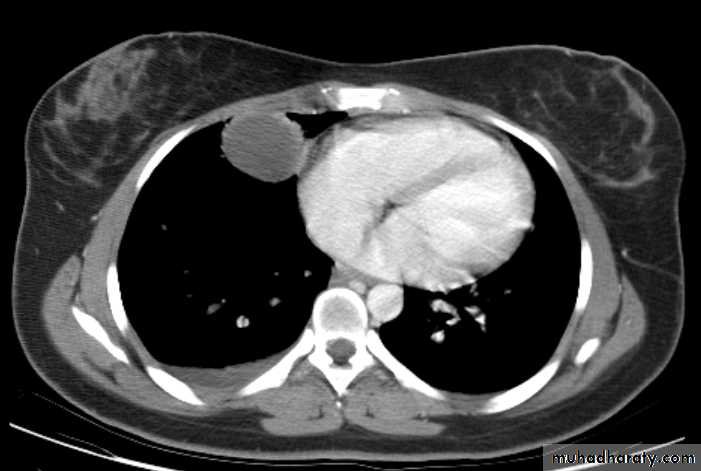

Hemothorax

X-ray hemothorax

X-ray pneumohemothorax